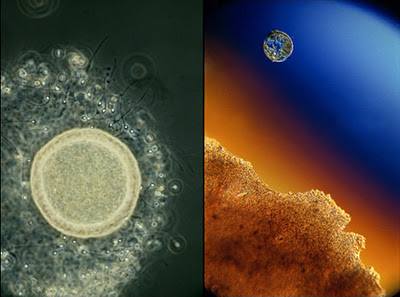

Ձվաբջիջը և սպերմատոզոիդները

Սաղմի զարգացման 22-րդ օրը: Մոխրագույնն ապագա գլխուղեղն է: